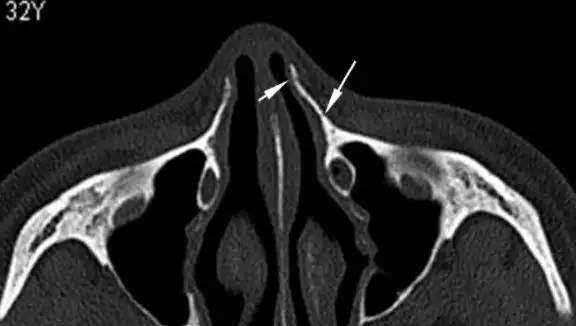

鼻骨横断位重组图像示左侧上颌骨额突骨折(长白箭头),无明显错位及